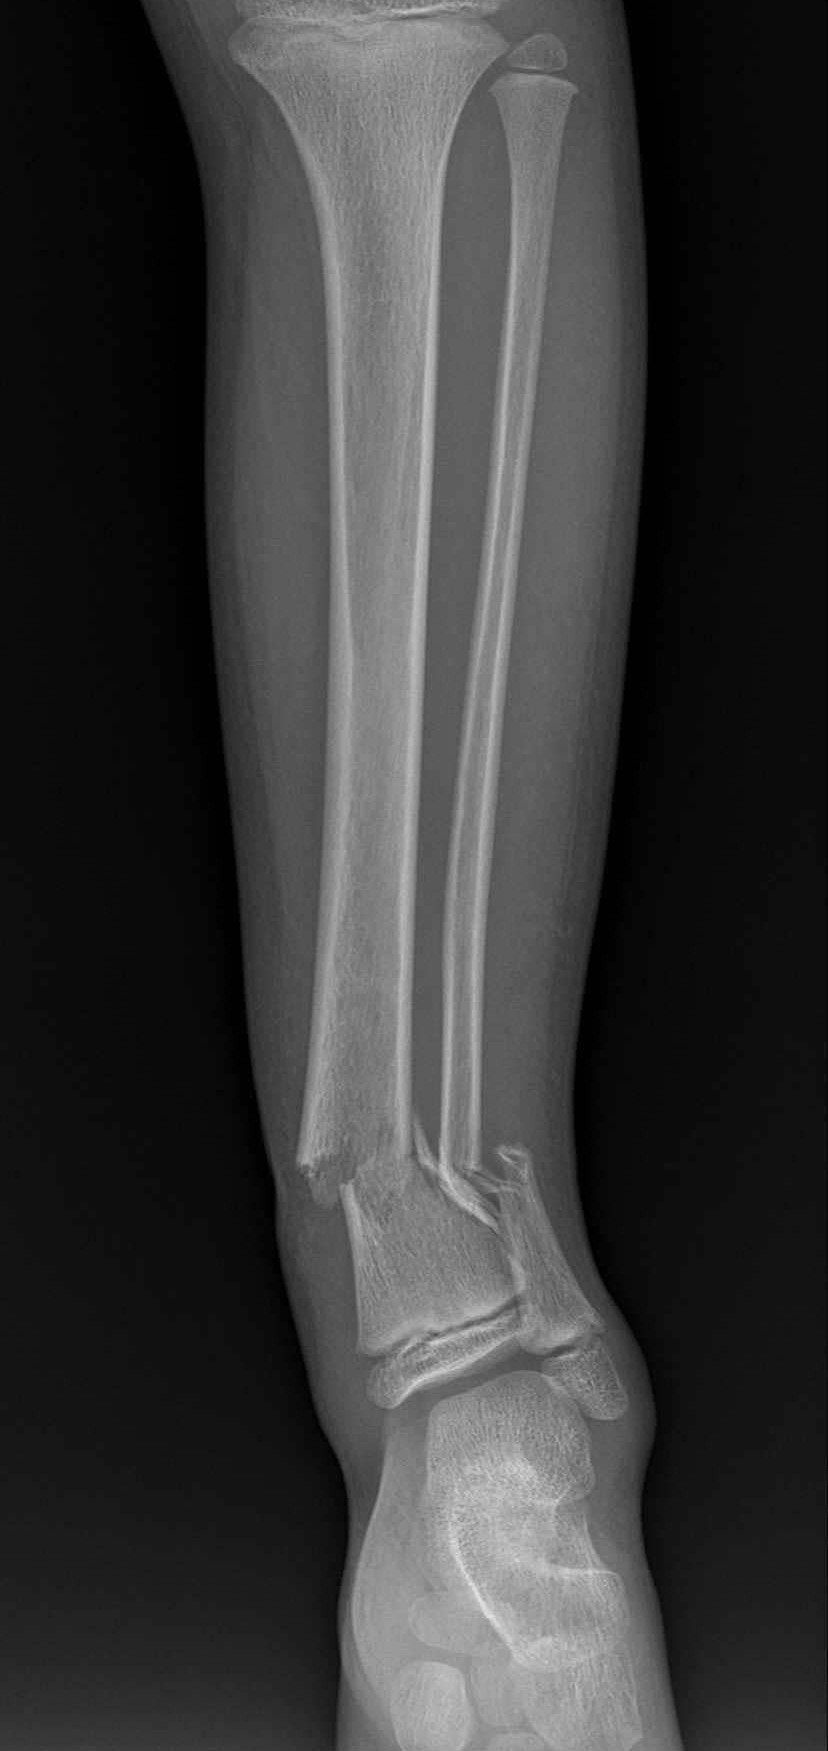

AI-Powered Fracture Detection & Classification

Upload X-ray images via drag-and-drop or select sample images for AI-powered fracture analysis.

Get instant AI diagnosis with confidence scores and medical recommendations in 5-10 seconds.

Review detailed findings and recommendations in the interactive canvas sidebar.

Advanced AI medical imaging tool developed at West Visayas State University for orthopedic fracture detection and classification.

Research-focused X-ray analysis system designed to assist medical professionals in diagnostic imaging.